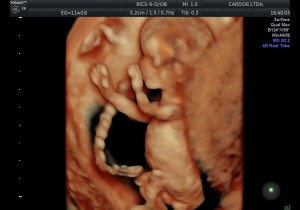

El desarrollo del feto varía en cada trimestre del embarazo.

En el primer trimestre, desde la concepción hasta las 12 semanas de la gestación, se forman los principales órganos del feto: corazón, intestino, estómago…

Vea la siguiente presentación. Imágenes 100% Cardor: